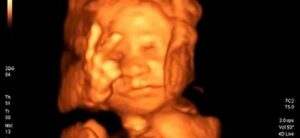

Хотя темпы роста постепенно замедляются, малыш все быстрее набирает вес. Если вы сделаете УЗИ на этом сроке, то уже можете увидеть крошечные ладошки, пальчики, разглядеть черты лица, возможно, узнать пол ребенка. Хотя некоторые малыши упорно не желают рассекречиваться, отворачиваясь от врачей.

Скорее всего, плановое второе УЗИ вы уже сделали или будете делать в ближайшее время. Вам уже скажут рост плода и его примерный вес.

Врач оценит развитие плода, сердцебиение, состояние околоплодных вод, проведет диагностику на предмет патологии. Очень часто мамы с нетерпением ждут это УЗИ и очень волнуются.

Зато, выйдя из кабинета «узиста» (возможно, даже с первой «фотографией» малыша) вы вздохнете полной грудью.

При нормально протекающей беременности дополнительных анализов сдавать на этом сроке не требуется, может быть назначено только УЗИ в 21 неделю, если мама не прошла его неделей раньше.

Проводимое на 21 неделе беременности УЗИ, скорее всего, позволит получить ответ на волнующих всех родителей вопрос, кто у них родится через несколько месяцев – сын или дочка. Но, разумеется, обследование назначается не с целью удовлетворения понятного любопытства родителей.

На УЗИ в 21 неделю обычно оценивают строение всех органов и систем плода, тщательно выслушивают сердцебиение плода и определяют строение сердца.

В это время обычно видно серьезные пороки и аномалии развития, что дает возможность уже сейчас заранее принять решение о том, как будут проходить роды и какой объем помощи нужно будет оказать ребенку.

Но обычно врач сообщает, что малыш развивается нормально, может посмотреть пол, хотя и не со 100%-ной вероятностью, бывают ошибки.Важно на УЗИ в 21 неделю оценить состояние плаценты и ее положение, кровоток и размеры плода. Это важно для оценки его развития.

Плод на 21-й неделе активно растет и развивается, он весит уже около 310-320 г, и теперь его длина будет измеряться от темечка до пяточек, она составляет в этот срок около 26 см.

УЗИ на 21-й неделе беременности